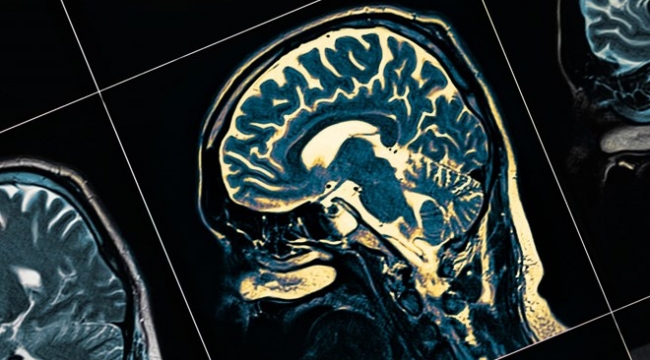

Alzheimer, sinir hücreleri ile düşünme becerileri arasındaki bağlantıları yavaşça bozan, geri dönüşü olmayan ve ilerleyen bir hafıza bozukluğuna neden olan hastlalığa deniliyor. Dünya Sağlık Örgütü'nün (DSÖ) 2019 verilerine göre dünyada demanstan muzdarip yaklaşık 50 milyon bulunuyor, vakaların yüzde 70’inde ise Alzheimer hastalığı sendromun nedeni olarak ortaya çıkıyor. Alzheimerı olan hastalar araba kullanmak, yemek pişirmek veya fatura ödemek gibi temel günlük işlerini yapmakta zorlanıyor.

Bu kapsamda, araştırmacılara göre metabolizma ve diğer biyolojik süreçlerin bir sonucu olarak, nöronlar sürekli biyolojik çöp üretiyor ve kararlı bir çöp atma sistemine ihtiyaç duyuyor. Eğer bu “çöp”ler nöronlardan uzaklaştırılmazsa, birikerek toksik hale geliyor ve beyin arızasına neden oluyor.

Gereksiz veya kusurlu proteinleri yok eden çok proteinli bir kompleks olan proteazom, nöronlar tarafından üretilen çöpün ana işlemcilerinden birini oluşturuyor. Ubiquitin-proteazom sistemi (UPS), proteinleri yeniden kullanmak ve üretmek için bir "biyolojik ürün işleme tesisi" olarak hareket ederek, hücre içi kalite kontrolü için temel bir mekanizma işlevi sağlıyor.

Eğer UPS arızalıysa, nöronlar "çöp kutularına" atılırken, yeni sentezlenen (bellek) ve yeni uzun süreli belleklerin oluşturulması için gerekli olan kullanılmış proteinler arasındaki denge bozuluyor ve sinir bağlantılarının kaybına (sinaptik başarısızlık) yol açan hafıza proteinlerinin eksikliği oluşuyor. Bu hasar başlangıçta beynin yeni anıların oluşması için hayati önemi olan bölümü olan hipokampusta meydana geliyor. Nöronlar ölürken beynin diğer kısımları da etkileniyor.

FASEB dergisinde yayımlanan araştırma, UPS inhibitörleri tarafından plastisite (bellek) proteinlerinin bozulmasının engellenmesinin Alzheimer'daki bellek kaybını tersine çevirebileceğini savunuyor. Bilim insanları, bellek proteinlerini yanlış bir şekilde kaldıran UPS sistemini kısmen bloke ederek, hafızanın anormal düzenlenmesini önlemeyi başardı.